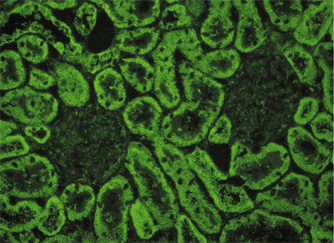

liver-kidney microsomes (LKM), ANA

mitochondria (AMA), LKM

liver

kidney

rat

rat